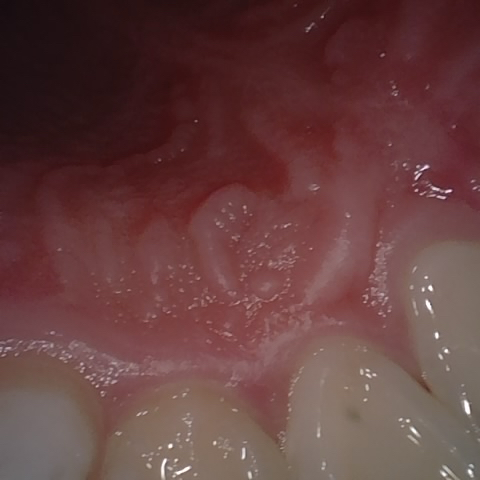

Annotated as "Good"

Original Image Rendering Image